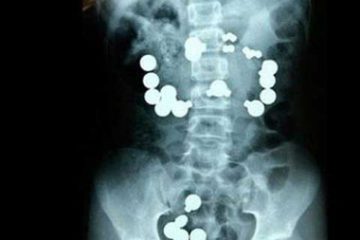

Cấp cứu cậu bé nuốt một chuỗi 42 viên nam châm

Các bác sĩ thực hiện ca phẫu thuật cho biết, họ đã cảm thấy rất lo sợ khi kết quả siêu âm phát hiện có tới 42 viên nam châm trong ...